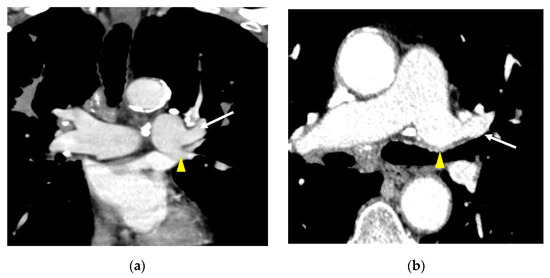

3. Results

3.2. Lobar and Segmental Supply Patternf of the AP

4. Discussion